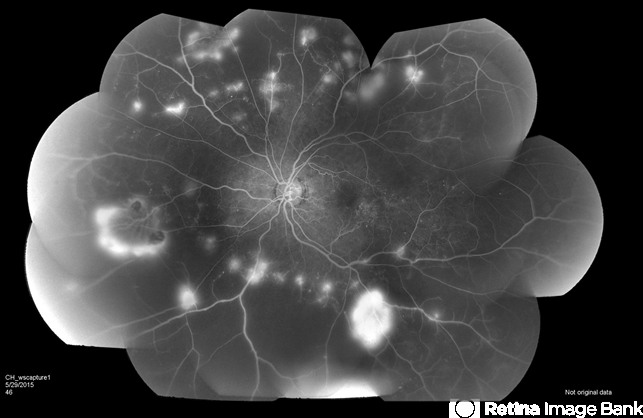

- proliferative diabetic retinopathy (PDR), neovascularization elsewhere (NVE), microaneurysms

- 61-year-old female with proliferative diabetic retinopathy, neovascularization, microaneurysms, dot blot hemorrhages and capillary nonperfusion.